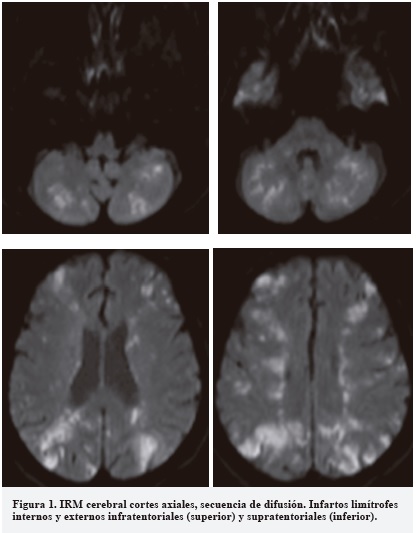

La IRM cerebral mostró eventos agudos isquémicos bilaterales tanto supra como infratentoriales (Figura 1). En la ecocardiografía se evidenció una fracción de eyección de 55% con un aneurisma del septum atrial con desplazamiento bilateral de 15 mm y un foramen oval permeable de 7 mm. El doppler de miembros inferiores fue normal.

The MRI showed bilateral supratentorial and infratentorial accute ischemic strokes (Figure 1). The echocardiogram showed an ejection fraction of 55% and an atrial septal aneurysm with bilateral excursions of 15 mm and a patent foramen ovale of 7 mm. The doppler ultrasound of lower extremities was normal.

La IRM cerebral mostró eventos agudos isquémicos bilaterales tanto supra como infratentoriales (Figura 1). El Doppler de vasos de cuello no mostró anormalidades significativas. El EKG mostró una elevación del segmento ST en precordiales V1-V3 y los niveles de troponina I fueron 1.66 ng/ml (0.0-0.05). En la ecocardiografía transesofágica se evidenció una fracción de eyección de 55%, con un aneurisma del septum atrial con desplazamiento bilateral de 15 mm y un foramen oval permeable de 7 mm. Con el fin de descartar trombosis venosa profunda como fuente de embolismo paradójico, se realizó un doppler de miembros inferiores en el que no se evidenció ninguna anormalidad. El videomonitoreo EEG mostró un enlentecimiento del ritmo de fondo con ausencia de ritmos fisiológicos y escasa variabilidad y reactividad.

Nuestra paciente tiene un pronóstico pobre en la medida en que tiene infartos limítrofes tanto internos como externos, supra e infratentoriales y, de acuerdo con la historia clínica y la apariencia radiológica, el mecanismo causal más probable es el compromiso hemodinámico (1, 5).